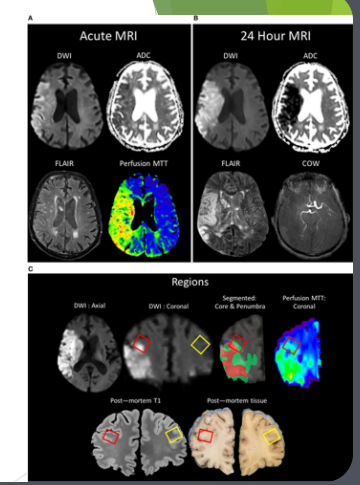

• Diffusion-weighted magnetic resonance imaging (DWRI)

• Diffusion-weighted magnetic resonance imaging (DWI or DW-MRI) is the use of specific MRI sequences as well as software that generates images from the resulting data that uses the diffusion of water molecules to generate contrast in MR images

• When do we use DWRI

• Look at brain activity in stroke patients

• Check for cancer tumours

• Application: Diffusion-weighted MRI used in medical imaging to assess brain activity and tumors.